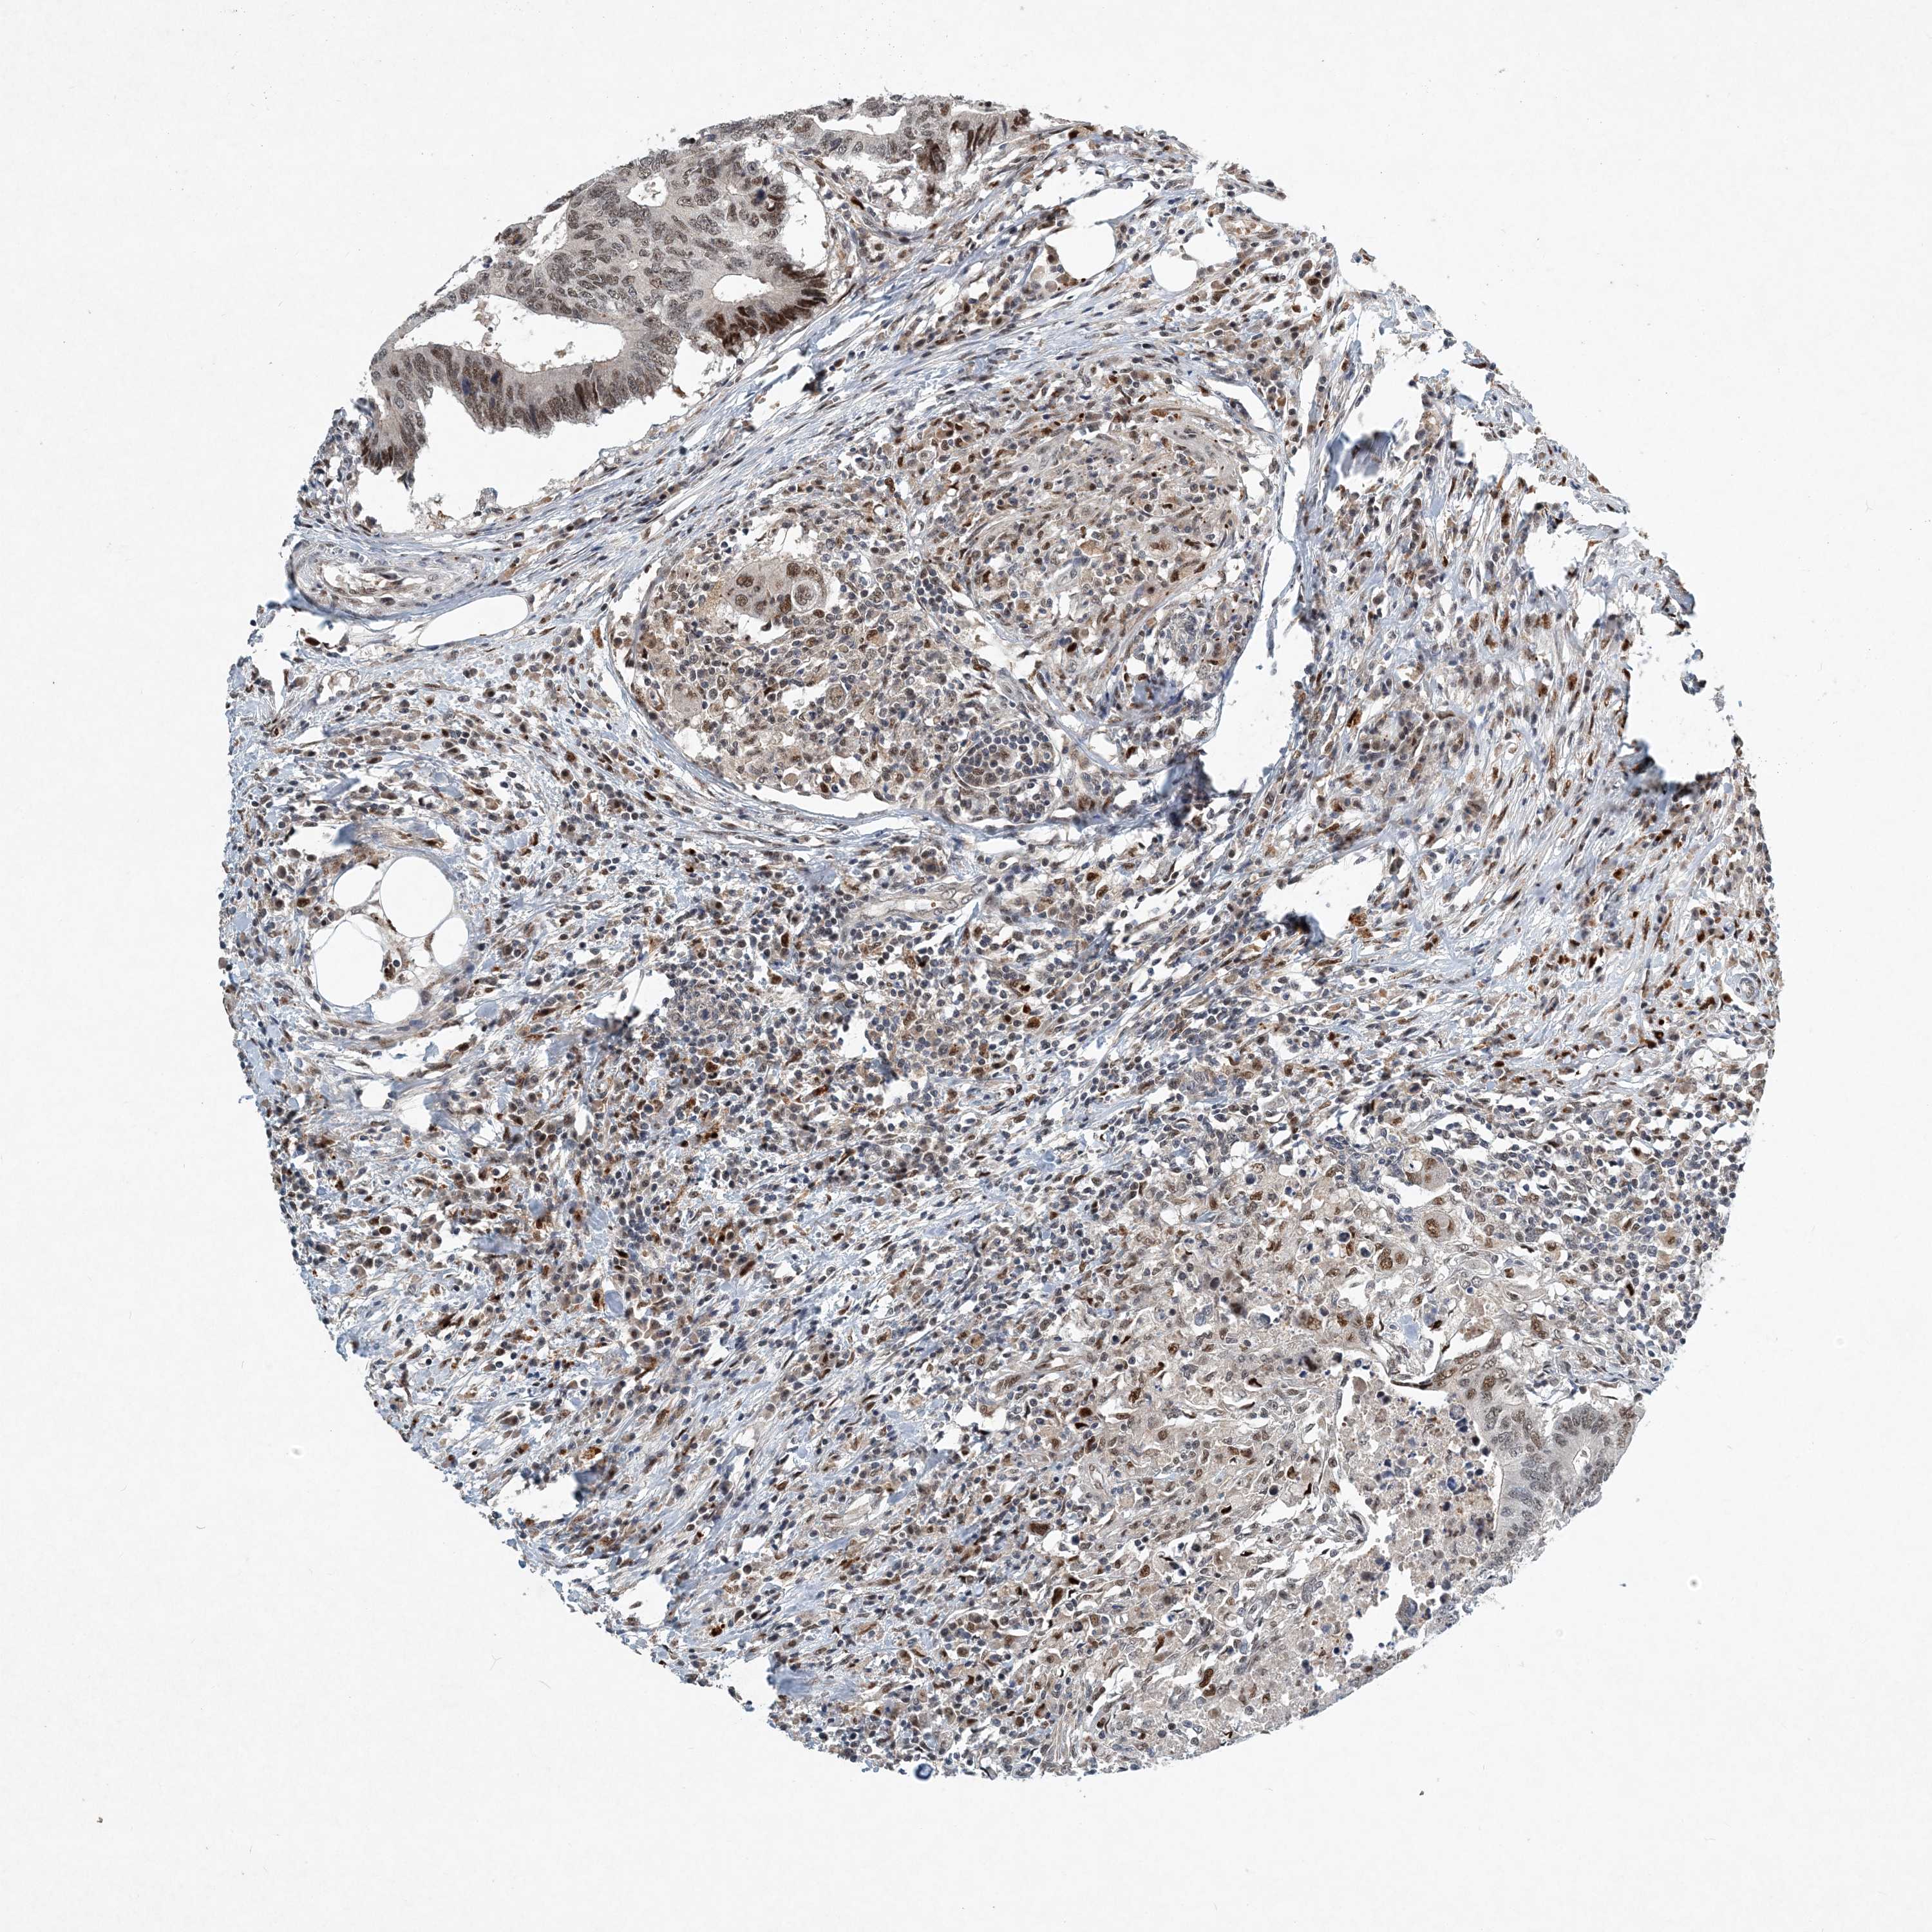

CANCER COLORECTAL CANCER Show tissue menu

Colorectal cancer

Human cancer

Colon adenocarcinoma